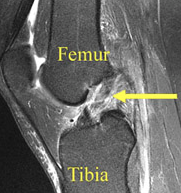

Primeramente por anamnesis, interrogando sobre el mecanismo lesional. Posteriormente, mediante la exploración clínica valoramos la inestabilidad articular. Finalmente, utilizando los métodos de diagnostico por imagen, principalmente la Resonancia Magnética (RM), nos ayudará a confirmar el diagnóstico.

Diagnóstico: